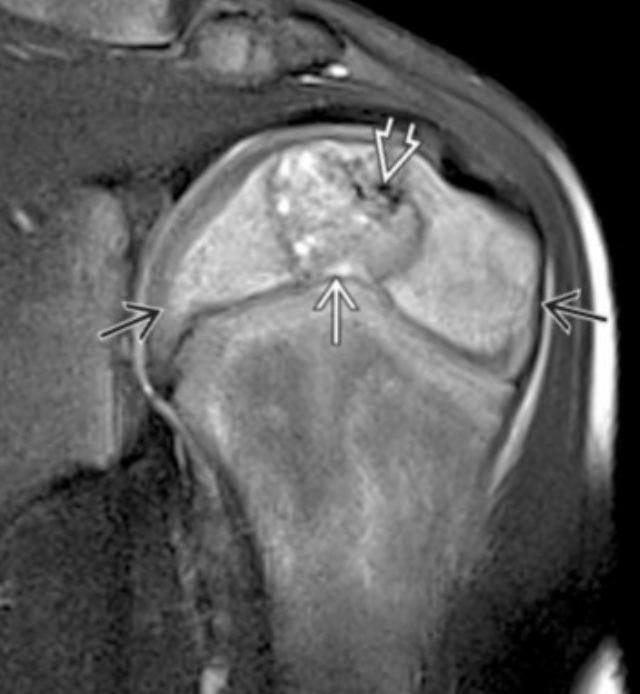

Synovial Sarcoma

• Misnomer as does not actually arise from synovium or in the joint but typically adjacent to joint

• Strong predilection for the extremities

• Relatively young 15-40 yo

• Slow growing and does not have to be painful

• Calcifications about 1/3 of the time

• Not required but commonly located next to a neurovascular bundle (popliteal space, anterior shoulder for example)

• Triple sign

• 3 different densities

• Looks like teratoma in the soft tissue, sometimes, other times just looks like a fucked up mass

• Split fat sign

• Very thin line of fat along periphery of mass, very subtle

• Heterogenous on MR with internal necrosis